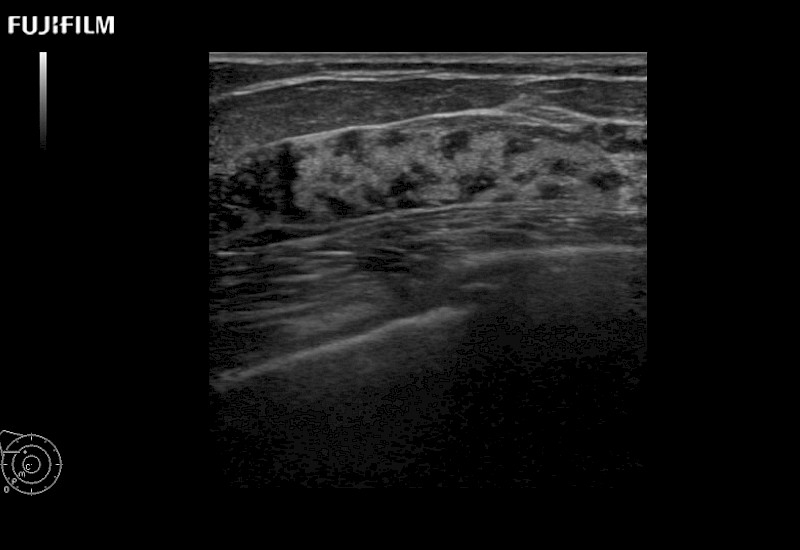

Linear array side-fire “T” transducer for open surgical procedures.